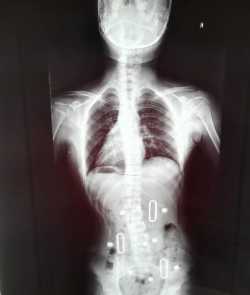

7月底,一位11岁女孩的母亲焦急的来到华人策略骨伤科就诊,希望骨科医生能帮忙纠正她女儿偏歪的脊柱。从脊柱全长像来看,孩子的胸腰椎严重侧弯,COBB’S角超过了40度,侧弯范围从胸5直至腰4,并伴有腰椎重度旋转畸形。之前她曾带着孩子前往多家医院就诊,得到的建议都是采用支具,并很有可能未来要采取手术治疗。母亲不愿幼小的孩子接受手术,中医骨科手法治疗是她最后的希望了。

孩子母亲带着复查的脊柱全长像前来复诊,影像显示在佩戴支具下,脊柱侧弯得到了明显的纠正,COBB’S角恢复到了18度,孩子的脊柱侧弯已经进入安全区了。看到这样的疗效,患者一家露出了满意的笑容,孩子和母亲也不再沮丧担心,终于破涕为笑。母亲说,当初她都不敢看那张X光片,如今心里像放下了一块大石头。真心感谢一附院骨伤科的医生,重新为孩子带来了健康和希望。(骨伤科供稿 通讯员 李庆)

矫正前后X光片